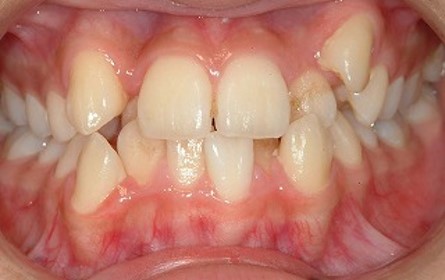

いくら歯磨きやフロスを頑張ったとしても、元々汚れが溜まりやすく、ケアが行き届かない歯並びというものがあります。それは「ガタガタの歯並び」「重なった歯並び」です。これを歯科では「叢生(そうせい)」と言います。

こちらに関しては良く分かりやすかと思います。歯並びが悪く、ガタガタしているので、歯と歯の重なっている場所に汚れが溜まりやすく、そして磨きにくいです。

このように重なってしまっている歯と歯の間には汚れが溜まりやすく、また汚れを取りずらそうなことが分かるかと思います。歯ブラシの毛先は入りませんので、フロスを使うことは必須となります。